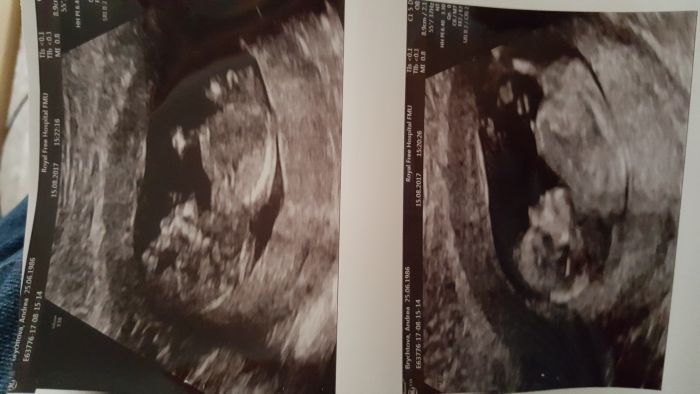

Mame za sebou screening, vsechno v poradku

. Uz se nemuzu dockat utz ve 20.tt, az se dozvime pohlavi

Ajinku krásné bříško

Gratulace k dobrým výsledkům, jak vidím tu fotečku, tak ti začínám závidět už doopravdy